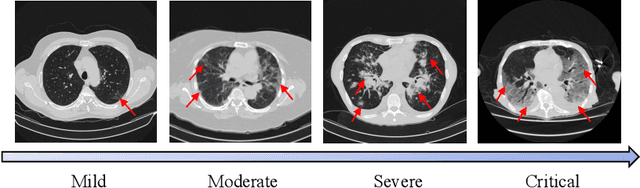

This paper presents our solution for the 2nd COVID-19 Severity Detection Competition. This task aims to distinguish the Mild, Moderate, Severe, and Critical grades in COVID-19 chest CT images. In our approach, we devise a novel infection-aware 3D Contrastive Mixup Classification network for severity grading. Specifcally, we train two segmentation networks to first extract the lung region and then the inner lesion region. The lesion segmentation mask serves as complementary information for the original CT slices. To relieve the issue of imbalanced data distribution, we further improve the advanced Contrastive Mixup Classification network by weighted cross-entropy loss. On the COVID-19 severity detection leaderboard, our approach won the first place with a Macro F1 Score of 51.76%. It significantly outperforms the baseline method by over 11.46%.